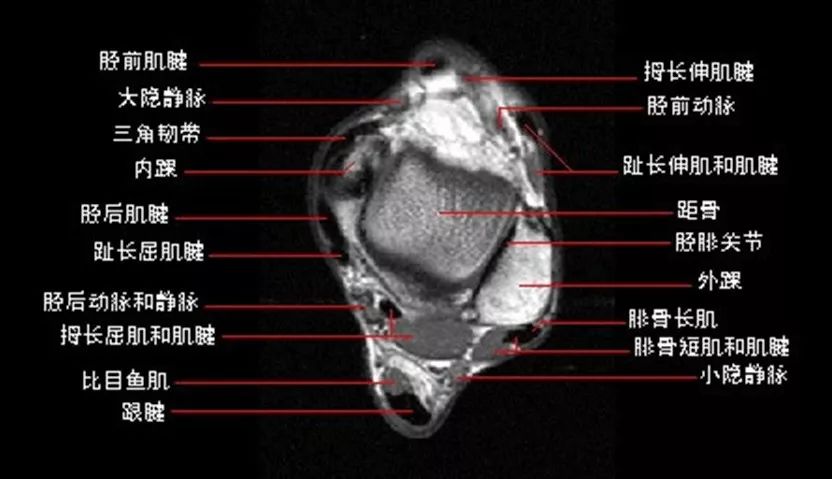

踝关节(anklejoint),由胫、腓骨下端的关节面与距骨滑车构成,故又名距骨小腿关节。胫骨的下关节面及内、外踝关节面共同形成的“冂”形的关节窝,容纳距骨滑车(关节头),由于滑车关节面前宽后窄,当足背屈时,较宽的前部进入窝内,关节稳定;但在跖屈时,如走下坡路时滑车较窄的后部进入窝内,踝关节松动且能作侧方运动,此时踝关节容易发生扭伤,其中以内翻损伤最多见,因为外踝比内踝长而低,可阻止距骨过度外翻。

踝关节解剖